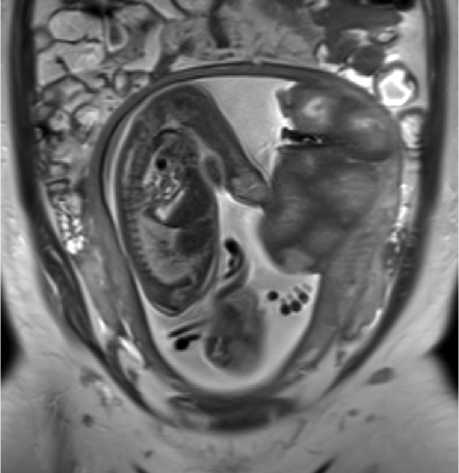

При наличии гипоинтенсивных зон характерной была подчёркнутая дольчатость плаценты (рис. 2), что не встречалось в группе изогипоинтенсивных зон: дольки плаценты визуализировались более отчётливо, были разделены толстыми септами ги-поинтенсивного МР-сигнала.

Рисунок 2. МРТ плаценты на 26 н.г., Т2-ВИ, корональная плоскость, диагноз – тяжёлая преэклампсия (пациентка № 11). По плодовой и материнской поверхностях плаценты определяются зоны гипоинтенсивного МР-сигнала с формированием широких междольковых перегородок и подчёркнутой дольчатости плаценты Figure 2. Placental MRI at 26 weeks of gestation, T2-WI, coronal plane, diagnosis – severe preeclampsia (patient 11). Zones of hypointense MR signal are observed along the fetal and maternal surfaces of the placenta, forming broad interlobular septa and pronounced lobulation